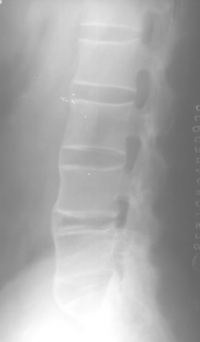

在脊柱方面主要表现在椎间盘、脊椎小关节、肋脊关节,后纵韧带寰枢关节。很少有上述关节出现病变而骶髂关节却不受侵犯。早期阶段,椎间盘纤维环浅层有炎症,伴反应性骨硬化与邻近椎体腐蚀,使椎体变成方形。纤维环逐渐骨化,并有骨桥形成。同时脊椎后关节和邻近韧带亦有类似的变化,最终脊柱完全融合,如竹节状(图96-10)。

强直性脊柱炎的患者还可以出现椎间盘周围椎体骨质腐蚀和硬化,竹节状改变亦在此节段中断,通常发生在疾病的后期。临床上常有急性发作,并有局限性疼痛。该区常有上述X线征象,称为"椎间盘炎"。这种病变易误诊断为结核化脓性骨髓炎,甚至认为是转移性病灶。